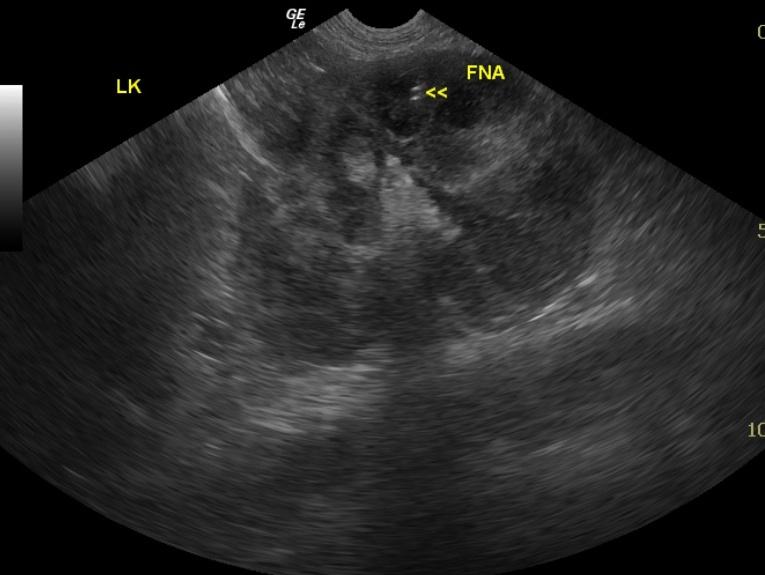

A 6-year-old female spayed Labrador Retriever dog was presented with upper gastrointestinal signs of 2 days’ duration. The patient was treated with antibiotics, gastroprotectants, and anti-emetics. Upper gastrointestinal signs continued despite the treatments, and the dog developed excessive panting and shaking. Blood chemistry revealed azotemia, hyperalbuminemia, and hyperphosphatemia. CBC revealed elevated hematocrit and elevated hemoglobin. Abdominal radiographs did not reveal any abnormalities. The dog was treated with IV fluids, however her azotemia continued to worsen despite treatment.